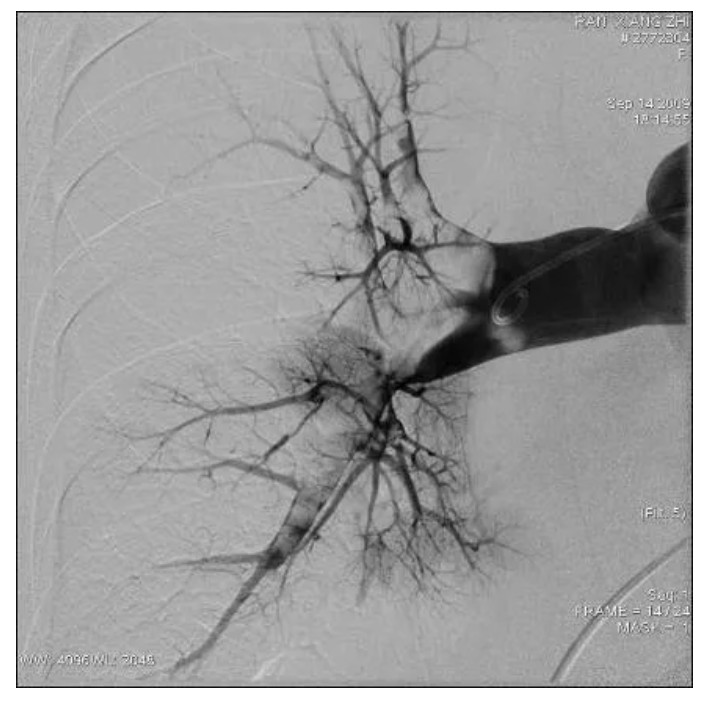

肺动脉造影提示提示充盈缺损

肺栓塞CT提示充盈缺损